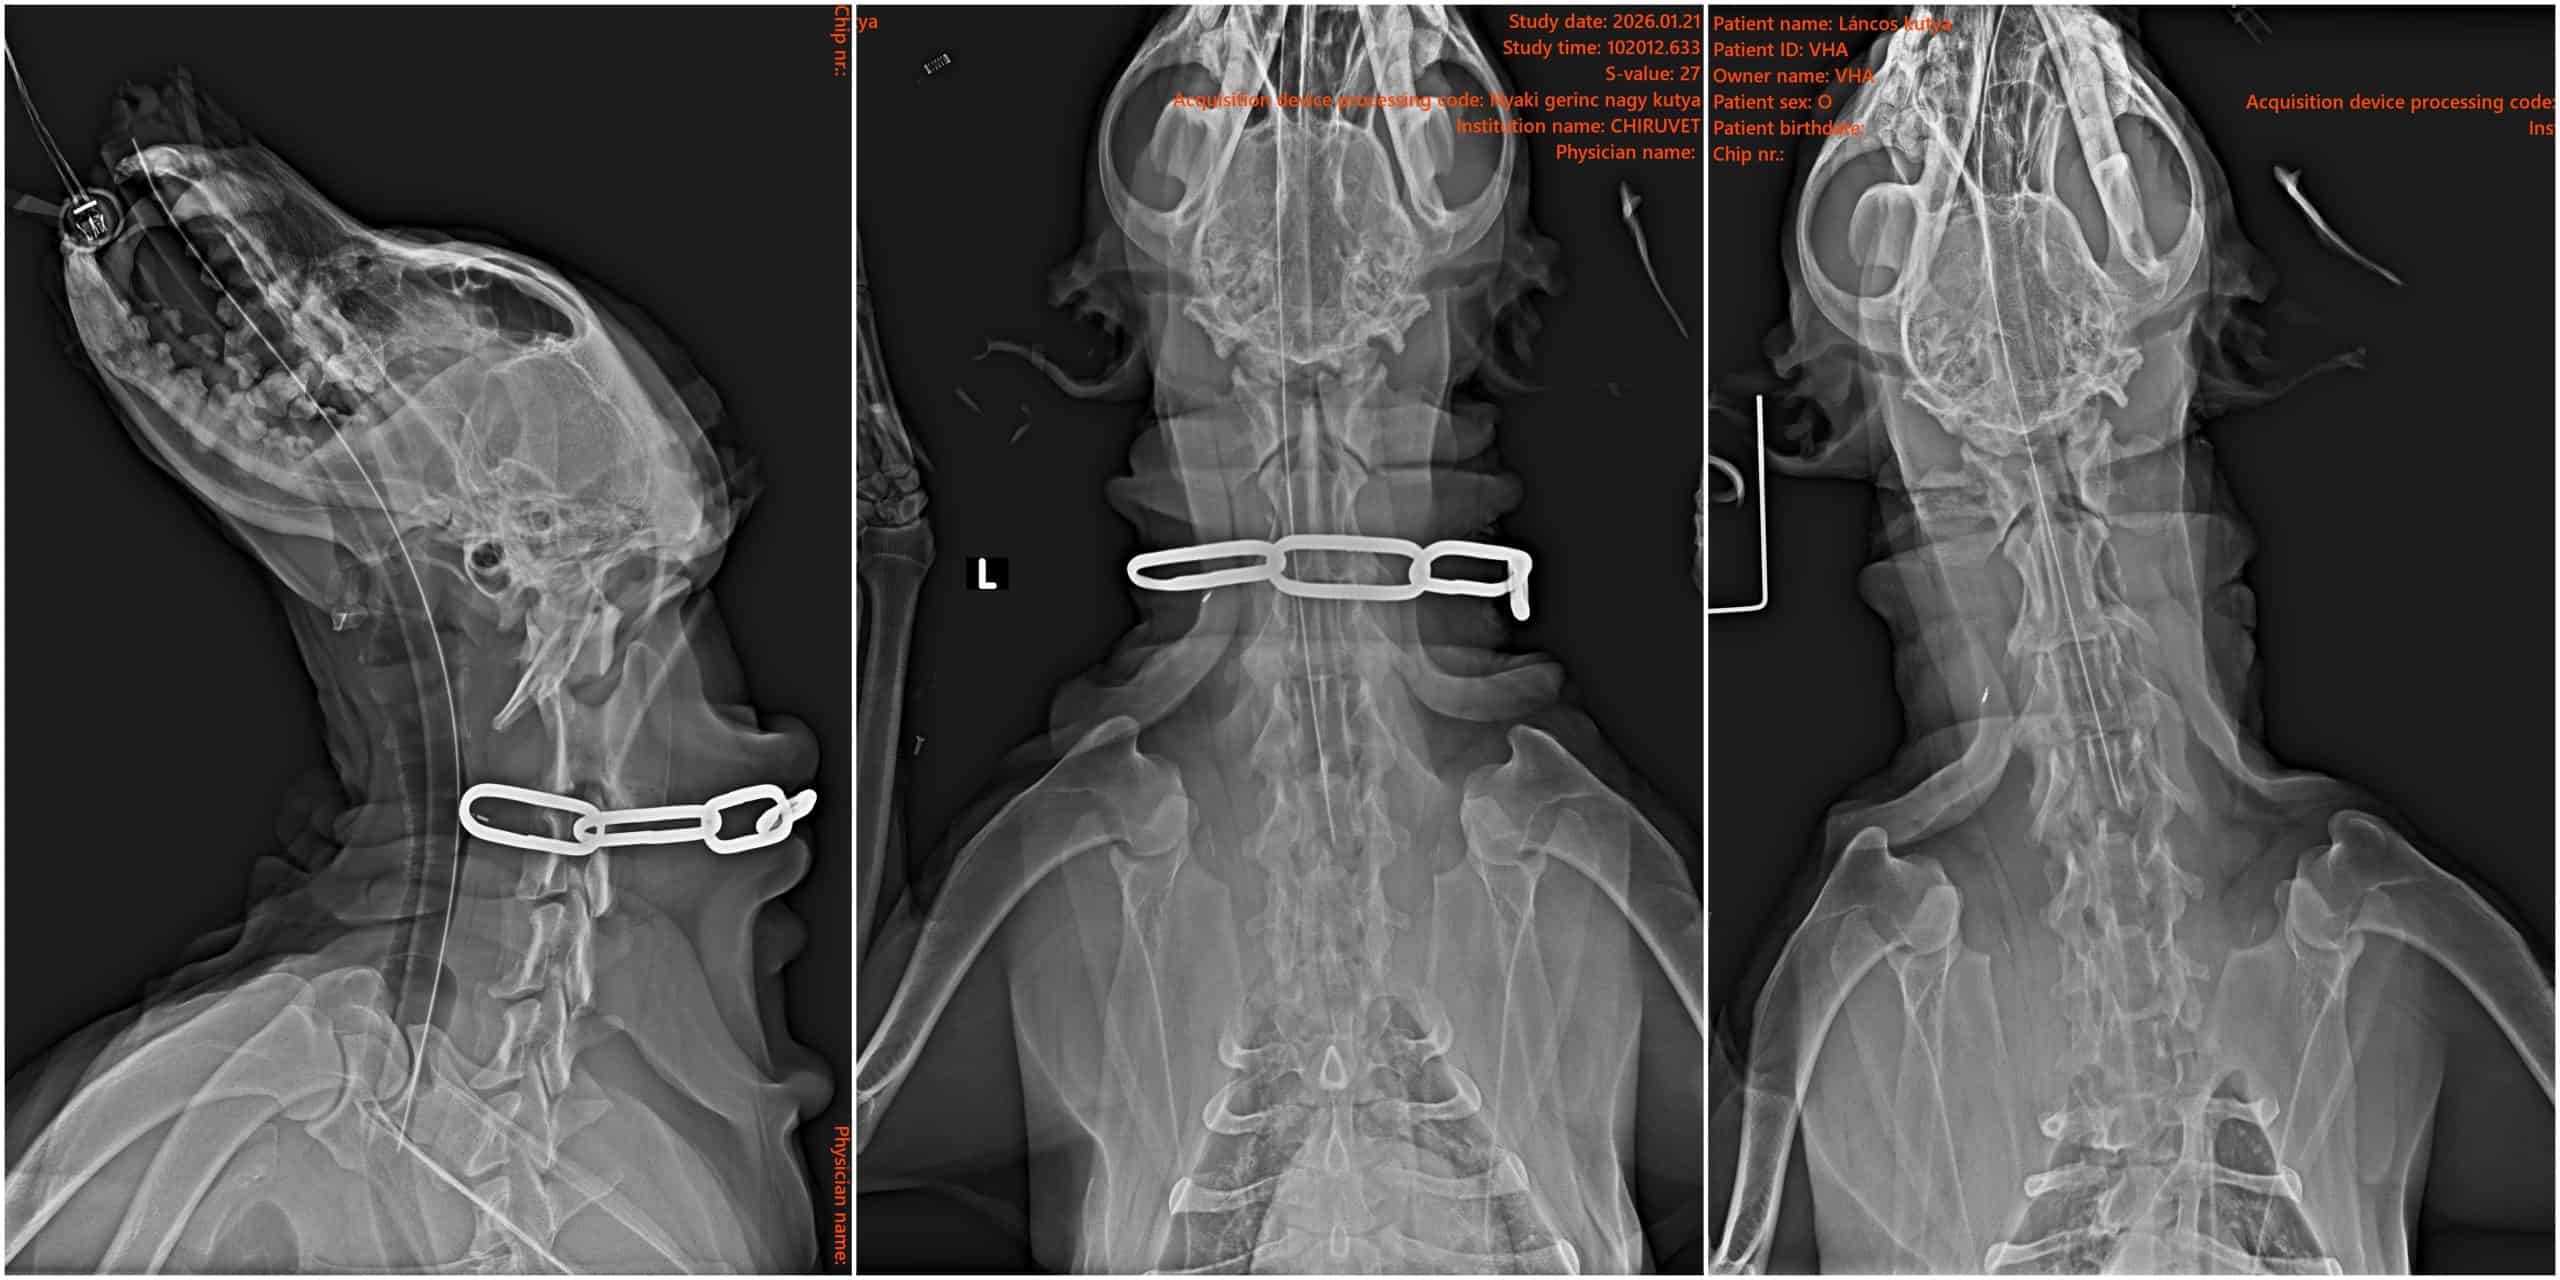

A szegény idős kutyát azonnal a Chiru-Vet Állatorvosi rendelőbe vittük, ahol az előzetes vizsgálatokat követően négy láncszemet (!) távolítottak el a nyaki szakasz bőréből, mélyen beágyazódva. (Valószínű, hogy szegény már évek óta szenvedhetett…)